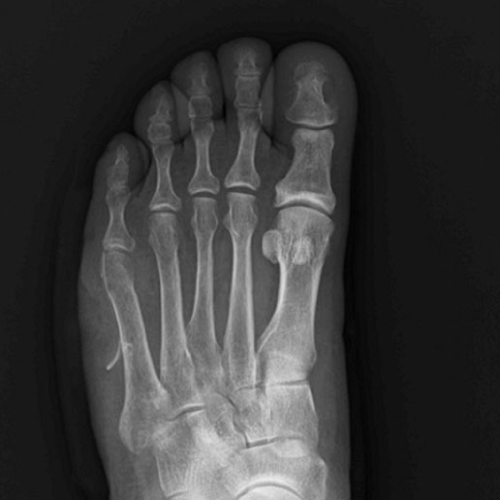

무지외반증

무지외반증의 '무지'는 엄지발가락을 말하고, '외반'은 몸의 중심에서 바깥쪽으로 멀어진 것을 뜻합니다.

엄지발가락의 제1중족 발가락 관절이 두 번째 발가락 쪽으로 과도하게 휘고 엄지발가락 관절 부위가 돌출되는 변형입니다.

무지외반증 증상

□ 외관성으로 엄지발가락이 휘어진 듯한 변형

□ 엄지발가락 관절 안쪽의 돌출 부위 통증

□ 두 번째, 세 번째 발가락의 발바닥에 굳은살과 통증

□ 심한 경우 엄지발가락이 두번째 발가락과 겹쳐짐